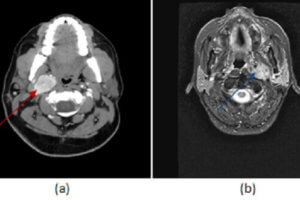

Parotid Lymphoma

Parotid masses are often seen incidentally on CT scans of the brain and neck. The most common primary parotid mass is the benign mixed tumor (also known as a pleomorphic adenoma). These... Read more »